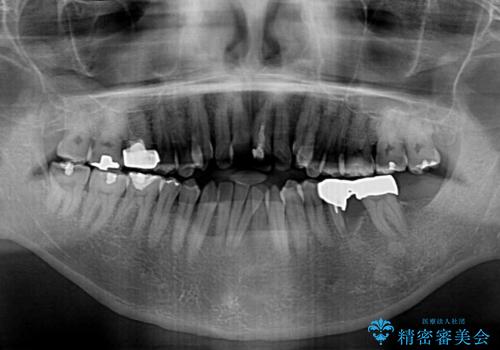

外科手術を併用した矯正治療を検討するほどに隙間の空いた開咬と、顕著な叢生が認められました。

開咬の改善には、舌の突出癖改善のためにトレーニングを行いつつ、インビザラインでの矯正治療が大変有効ですが、上顎骨が下顎骨に対して前方位に位置しており、インビザライン単独で治療を行うよりは補助装置とワイヤー矯正で奥歯の咬み合わせを改善してから、開咬改善のためのインビザライン矯正治療を行うこととしました。

奥歯の銀歯は、土台の一部に抜歯が必要であったので、矯正治療の途中で抜歯してからオールセラミックブリッジによる補綴治療を行うこととしました。